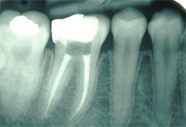

Доступ к пульповой камере врач-стоматолог получает, удалив ткани дентина, пораженные кариесом. Далее, специальными инструментами для обработки каналов, происходит очистка корневого канала от пораженной ткани пульпы. Дезинфицирующими растворами обрабатываются стенки канала для удаления оставшихся микробов и предотвращения дальнейшего роста инфекции. На протяжении всего процесса лечения проводятся рентгенологическая диагностика хода лечения и состояния канала до и после лечения. Высушив канал от растворов, доктор проводит заполнение канала пломбировочным материалом – гуттаперчевыми штифтами, которые при нагревании заполняют все полости и микропоры.